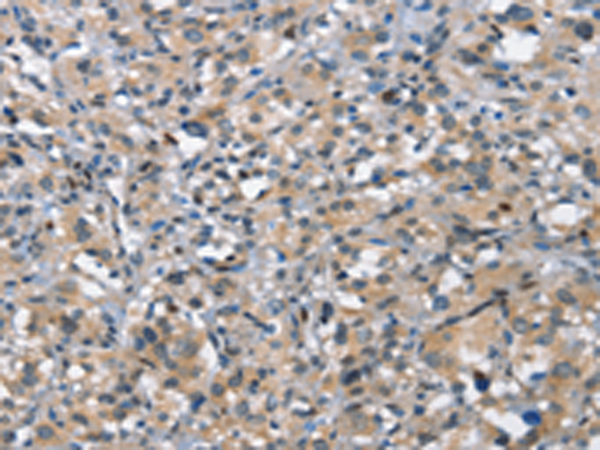

分类: 科研抗体货号: P11248别名: TKT; MIG20a; NTRKR3; TYRO10应用: IHC反应种属: Human, Mouse